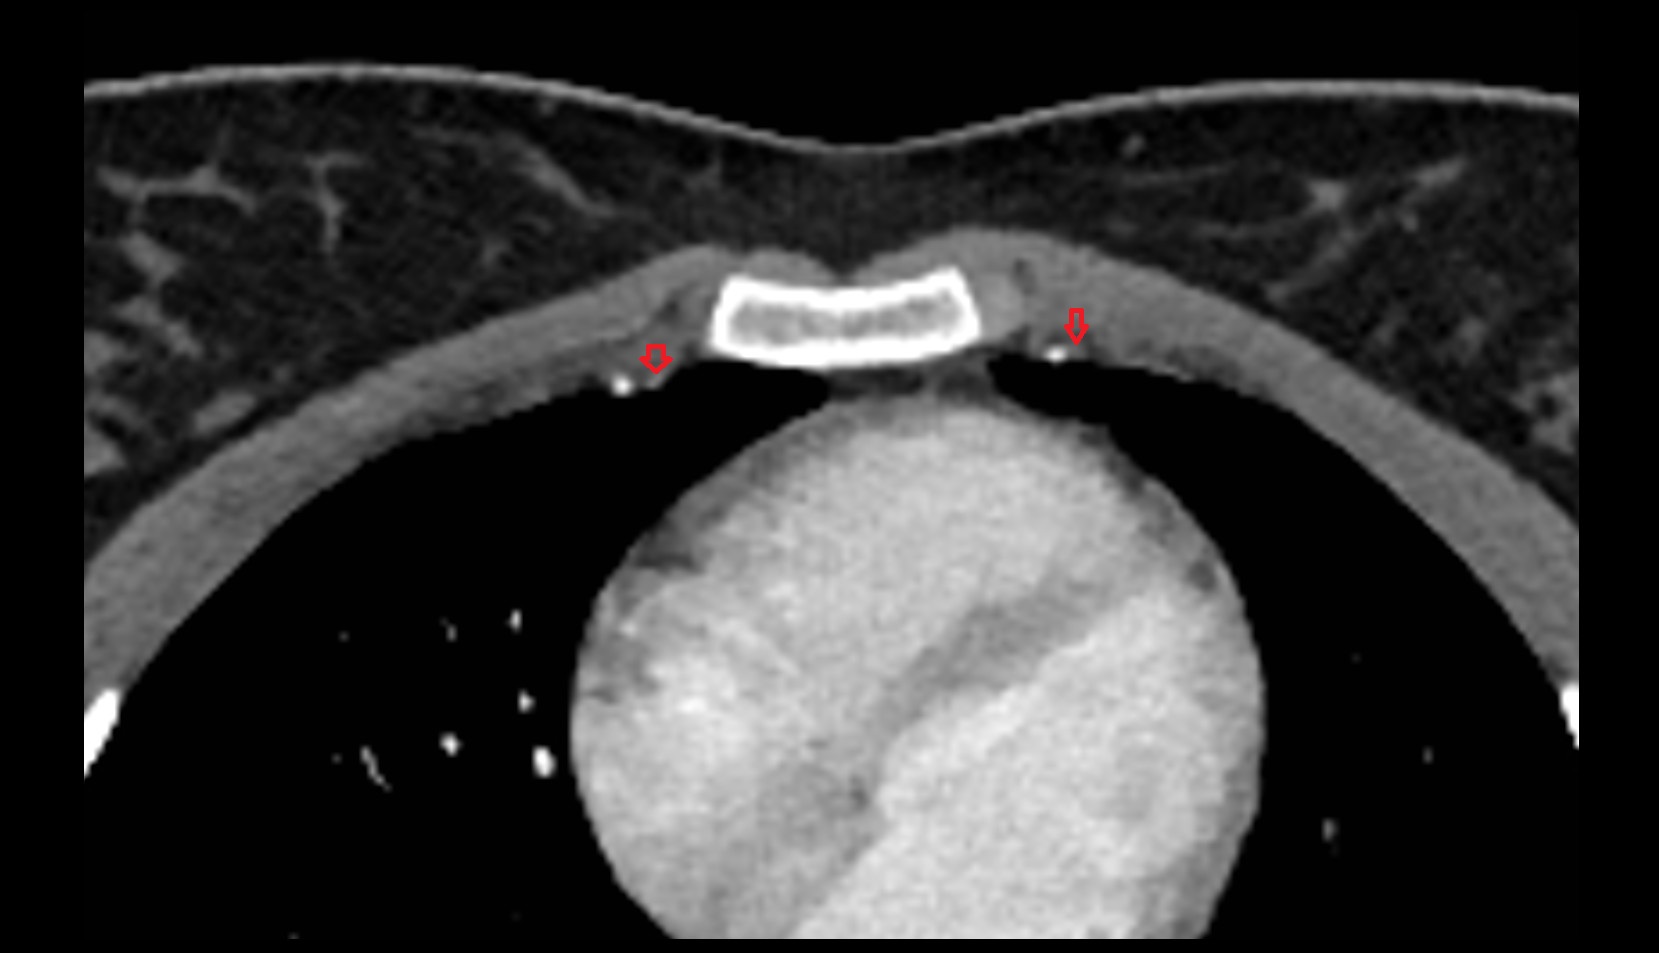

- Sternocostal synchondrosis of first rib

- Sternoclavicular joint

- Sternal end of the clavicle